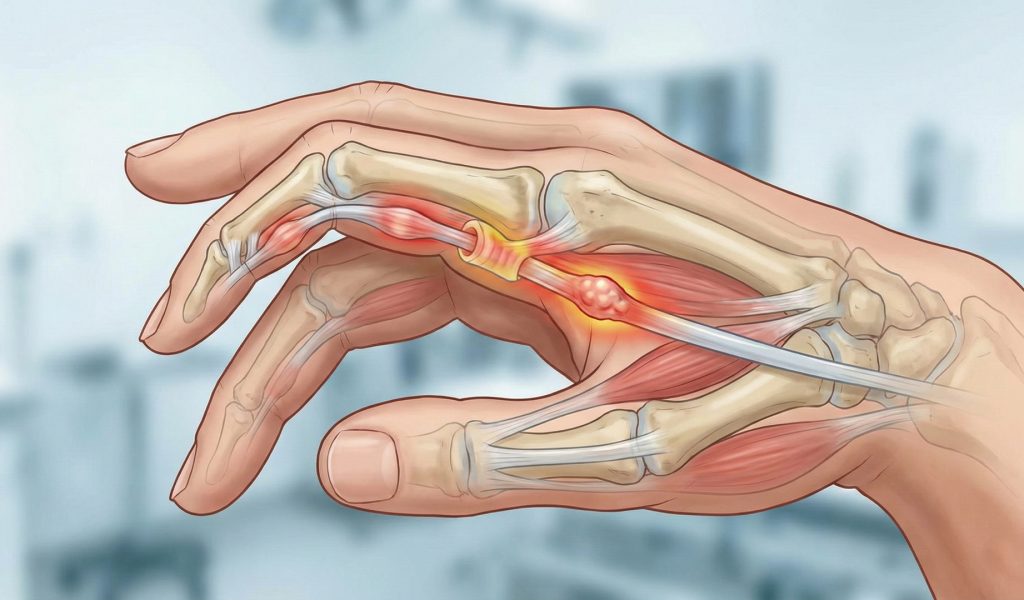

Tetik parmak, parmak tendonlarının geçtiği kanalda sıkışması sonucu parmağın açılıp kapanırken takılması ya da kilitlenmesiyle ortaya çıkan bir el hastalığıdır. Özellikle sabahları parmakta sertlik, ani açılma sırasında ağrı ve “klik” sesi ile kendini gösterir.

Tetik parmak, parmak tendonunun kalınlaşması ve tendon kılıfının daralması sonucu gelişir. Bu durum tendonun rahat hareket etmesini engeller.

Tetik Parmakta Tedavi Nasıl Planlanır?

Tetik parmak tedavisi, hastalığın evresine göre planlanır. Erken dönemde cerrahi dışı yöntemler etkili olabilir.

İlaç ve enjeksiyon tedavileri